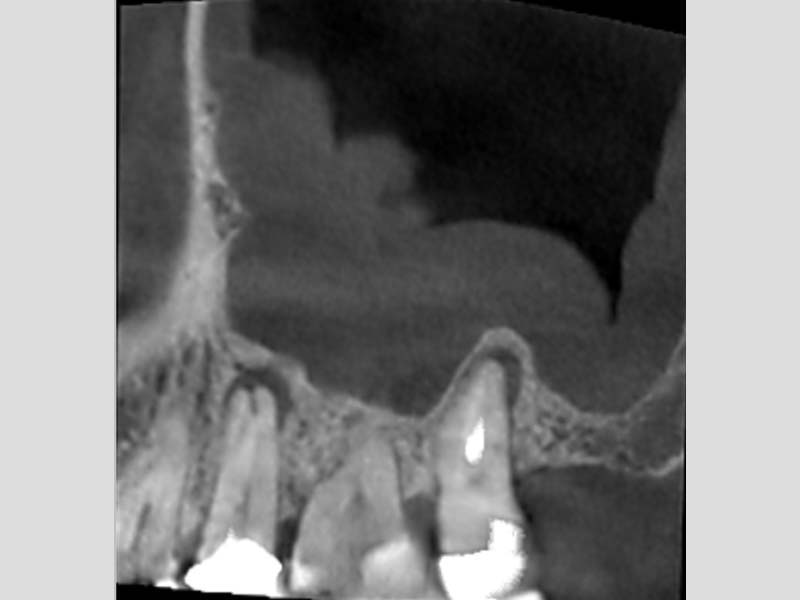

圖例為案例分享:

粉:感染增生的鼻竇黏膜

綠:原本的鼻竇範圍

紫:牙齒跟監感染,進入鼻竇

術前的電腦斷層